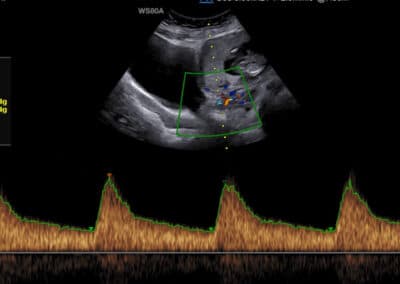

Dopplerovské vyšetření průtoku krve v děložní tepně maminky (arteria uterina) ve 12.týdnu těhotenství

anamnestických údajů maminky (výška, váha, kouření, cukrovka, vysoký krevní tlak, předchozí těhotenství, autoimunitní onemocnění) krevního tlaku maminky v den vyšetření změřeného dvakrát na každé ruce vyšetření koncentrace PAPP-A (a případně PlGF) v krvi maminky Dopplerovského vyšetření děložních tepen maminky